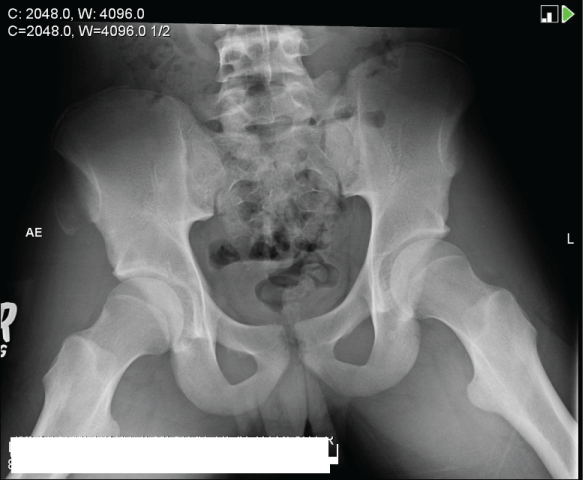

A 15 year-old male, with no significant past history presented to the ED with right hip pain. Two weeks prior, he attended a concert in a mosh pit, noting right hip pain for 2 days following the event. He did not seek medical attention and was able to ambulate. The pain gradually resolved with rest and ibuprofen. He resumed his mosh pit activity one day prior to presentation, where he stated that he heard a crack in his right hip. He was unable to ambulate at the scene. He reported a non-radiating pain, with a score of 8/10, worsened when lying down and improved with sitting. Vital signs were as follows: Temperature 36.77°C (98.2°F), heart rate 68 beats/minute, blood pressure 128/70mmHg, respiratory rate 18, and oxygen saturation 99% room air. Examination of his right hip revealed tenderness to palpation over the joint and a decreased range of movement at his hip joint. His plain radiograph of the pelvis revealed an avulsion fracture of the right anterior superior iliac spine (Figure 2).